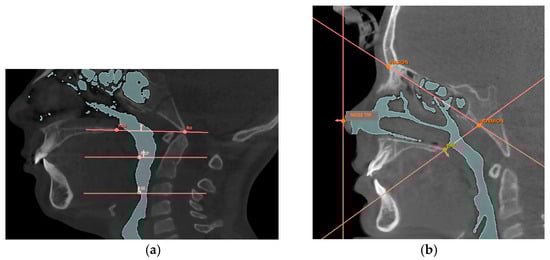

| Reference Point | Description |

|---|---|

| Nose tip | The most anterior point of the nose |

| PNS | Posterior nasal spine, the most posterior point of the hard palate |

| Hormion [42] | Point where the posterior border of the vomer articulates with the sphenoid bone |

| Nasion | The most anterior point of the fronto-nasal suture |

| BA | Basion, the lowest point of the anterior border of the foramen magnum |

| PISP | Posteroinferior point of the soft palate, the most posterior and inferior point of the soft palate |

| SE | Superior point of the epiglottis, the uppermost point of the epiglottis |

| Planes | Description |

| Nasal Perpendicular | Vertical plane passing through the tip of the nose |

| Hormion-PNS | Plane passing through the Hormion point and the PNS point |

| Hormion-Nasion | Plane passing through the Hormion point and the Nasion point |

| Ba-SPN [43] | Plane passing through the Ba point and the PNS point |

| Soft palate plane [43] | Horizontal plane passing through the PISP point |

| Epiglottis plane [43] | Horizontal plane passing through the SE point |